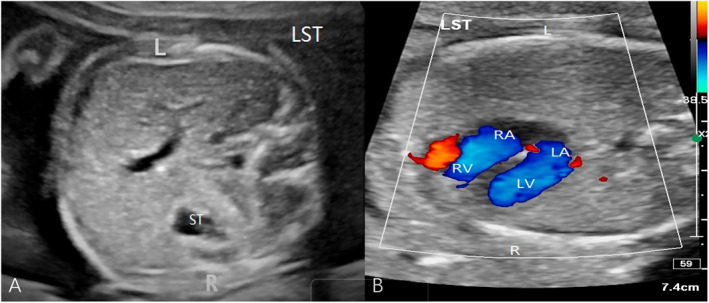

Objective: To investigate the distribution of laterality defects in fetuses, including situs inversus totalis (SIT) and situs ambiguous (SA), and to explore the potential genetic etiology of these laterality defects.

Methods: Detailed fetal echocardiography and extracardiac structural evaluations were performed. Genetic testing, including chromosomal microarray analysis, and trio exome sequencing was conducted to identify potential genetic variants.

Results: The incidence of heart malformation was significantly higher in SA fetuses than in SIT group (30/31 vs. 2/36, p < 0.001). The incidence of univentricular heart with single atrium was significantly higher in right isomerism compared with left isomerism (12/19 vs. 3/12, p = 0.029), while the incidence of double outlet right ventricle was significantly higher in left isomerism (5/12 vs. 1/19, p = 0.022). Genetic testing identified variation within candidate genes of cardiac development. Except for CFAP300 c.604delG and KMT2D c.16351T>C, which were rated as "likely pathogenic", all other variants were categorized as variants of uncertain significance, with some fetuses having compound heterozygous variations.

Conclusion: Fetuses with SA have a significantly higher likelihood of concurrent heart malformations compared with those with SIT. Genetic testing identified potential genetic variants that may play crucial roles in the mechanisms underlying normal fetal visceral positioning. Further studies are needed to explore the clinical significance of these genetic variants and to improve our understanding of the etiology and management of fetal laterality defects.